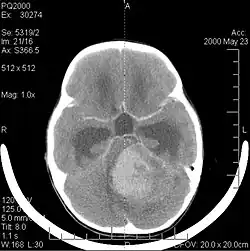

La tomodensitométrie (TDM) et L'imagerie par résonance magnétique (IRM) peuvent détecter efficacement une néoplasie dans le cerveau. L'IRM est plus sensible que la TDM pour identifier les lésions, mais présente des contre- indications pour les patients porteurs de stimulateurs cardiaques, de prothèses incompatibles, de clips métalliques et contre-indications. La TDM reste la méthode de choix pour détecter les calcifications au sein des lésions ou les érosions osseuses de la calotte ou de base du crâne. L'utilisation d' agents de contraste, iodés dans le cas du scanner et paramagnétiques (gadolinium) dans le cas de l'IRM, permet l'acquisition d'informations sur la vascularisation et l'intégrité de la barrière hémato-encéphalique, une meilleure définition de la tumeur tumorale par rapport à l' œdème environnant et à la génération d' hypothèses sur le degré de malignité. L'examen radiologique permet également d'évaluer les effets mécaniques et les modifications importantes des structures cérébrales résultant de la tumeur, telles que l' hydrocéphalie et les hernies, dont les effets peuvent être fatals. Enfin, en préparation à la chirurgie, ce diagnostic peut être utilisé pour déterminer la localisation de la lésion ou l'infiltration de la tumeur dans des zones vitales du cerveau. À cette fin, l'IRM est plus efficace que la tomodensitométrie car elle peut fournir des images en trois dimensions.

La tomodensitométrie du cerveau montre généralement une masse tissulaire qui peut être améliorée par l'un ou l'autre contraste. Au scanner, les gliomes de bas grade apparaissent généralement isodenses au parenchyme normal et peuvent donc ne pas présenter de rehaussement de contraste. De même, les lésions de la fosse crânienne postérieure sont difficiles à identifier au scanner. Par conséquent, les seuls résultats d'une telle tomographie ne sont pas toujours suffisants à des fins diagnostiques. Dans les cas douteux, l'utilisation de l'imagerie par résonance magnétique plus sensible est indispensable.

Sur-L'IRM montre une tumeur intracrânienne comme une lésion massive qui peut devenir plus luminescente après utilisation du produit de contraste. Cependant, il y a toujours une anomalie de signal dans -L'imagerie par résonance magnétique, qui indique la présence d'une néoplasie ou d'un œdème vasogénique. Habituellement, une luminescence accrue (amélioration du contraste) indique une tumeur d'un grade supérieur de malignité. Un anneau de contraste est caractéristique du glioblastome, avec la partie luminescente correspondant à la partie vitale de la tumeur maligne, et la plus foncée - zone hypointense correspondant à une nécrose tissulaire.

Les métastases cérébrales sont les néoplasmes intracrâniens les plus courants chez les adultes, étant dix fois plus fréquents que les tumeurs cérébrales primaires. Ils marchent à 20 jusqu'à 40 pour cent des adultes atteints de cancer et sont principalement associés au cancer du poumon et du sein et au mélanome . Ces lésions résultent de la propagation des cellules cancéreuses dans la circulation sanguine et surviennent le plus souvent à la jonction de la matière grise et blanche, où la section transversale des vaisseaux sanguins change, emprisonnant les embolies de cellules tumorales . 80 % des lésions surviennent dans les hémisphères cérébraux, 15 pour cent dans le cervelet et 5 pour cent dans le tronc cérébral. Environ 80 % des patients ont des antécédents de cancer systémique et 70 pour cent ont de multiples métastases cérébrales.

Des progrès significatifs ont récemment été réalisés dans le diagnostic et le traitement de ces lésions, entraînant une amélioration de la survie et du contrôle des symptômes. L'apparition des signes et des symptômes est similaire à celle d'autres lésions massives du cerveau. La méthode de diagnostic de choix est l'imagerie par résonance magnétique utilisant des produits de contraste.